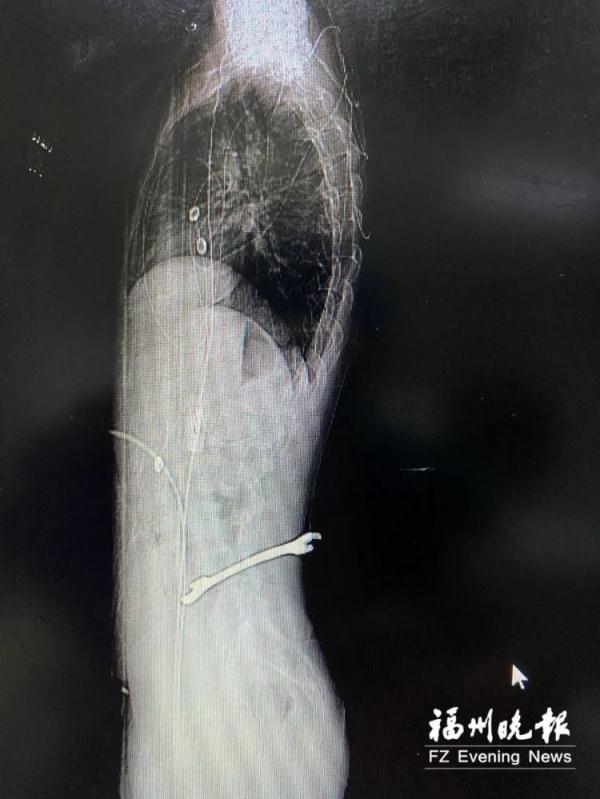

很快,小王被送進福州市第二總醫院急診科搶救室。進一步檢查顯示,小王傷情非常棘手,扳手較大一頭從他后背正中偏右位置貫入,斜插入脊柱,徑直穿過椎體左前方,穿入腹腔甚至將緊貼的髂血管頂得移位。

“手術最大的風險,就是不確定緊挨扳手的髂血管是否已經出現損傷,一旦這根手指粗的血管在取異物過程中破裂,血液會噴涌而出,隨時有生命危險。”

前來會診的脊柱外科劉伯齡主任分析

經過討論,最后決定脊柱外科先取異物;一旦發生血管損傷,血管外科迅速采取介入手術堵塞止血;胃腸外科處理腹腔損傷;神經外科修復受損神經……

終于被順利取出

血管毫發無損

手術直到次日凌晨2點多才結束,隨后小王被送入重癥病房進一步觀察治療。術后次日,小王左側肢體的麻木感明顯減退。專家們將在后期為其制定康復方案,盡力幫助他恢復活動能力。